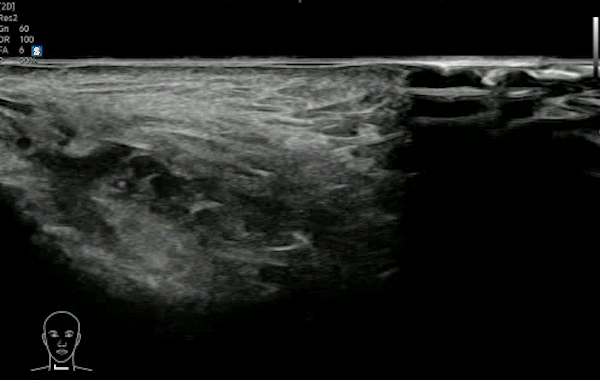

히알라제(테르가제)는 히알루론산(HA)을 분해하는 효소로, 히알루론산 필러를 녹이는 데 사용됩니다. 초음파로 필러의 정확한 위치·층·분포를 확인한 뒤, 초음파를 보면서 목표 부위에 맞춰 주입하면 ‘필러가 없는 곳에 주사해 효과가 떨어지는 상황’을 줄이고 보다 정밀한 교정을 기대할 수 있습니다. ※ 시술 적용 여부는 필러 성분(히알루론산 여부)과 조직 상태에 따라 달라질 수 있습니다.

시술 전 초음파 검사로 필러의 정확한 위치·층·분포를 확인해 ‘어디를 녹일지’부터 정밀하게 설정합니다.

STEP 02초음파 검사시술 전 초음파로 필러의 위치·양·주입된 층을 확인해 ‘어디를 녹일지’부터 정확히 설정합니다.

STEP 04정밀 주입/모니터링실시간으로 초음파로 보며 히알루론산을 분해하는 효소를 주입해 히알루론산 필러를 교정합니다. 초음파로 실시간으로 보면서 시술하기 때문에 정확하고 안전합니다.